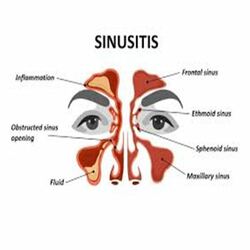

Acute & Cronic sinusitis

When fluid builds up in the air-filled pockets in the face it is referred to as Sinus infections. This fluid build-up allows germs to grow. Viruses cause most sinus infections, but bacteria can also cause some sinus infections.There are two main types of sinusitis is Acute and Chronic.

Acute sinusitis is inflammation that lasts for less than 4 weeks, subacute sinusitis lasts from 4 to 12 weeks, while chronic sinusitis lasts for more than 12 weeks.

Common signs and symptoms of chronic sinusitis include:

- Nasal inflammation.

- Thick, discoloured discharge from the nose (runny nose)

- Drainage down the back of the throat (postnasal drainage)

- Blocked or stuffy (congested) nose causing difficulty breathing through your nose.

- Bad breath.

- Loss of smell or taste.

Some people are more prone to Sinusitis

- People who have allergies.

- People who have structural problems with their noses (like a deviated septum) or polyps, which are growths that can hang inside noses or sinus cavities.

- People who spend a great deal of time in places where infections happen, like preschools or day cares.